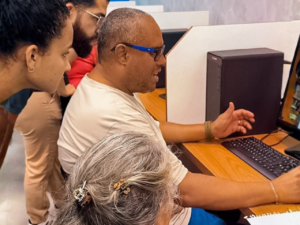

As turmas do 6º, 7º e 8º semestres de Medicina Veterinária tiveram a oportunidade de participar de uma palestra sobre Raio x em animais de pequeno porte e silvestres, com o técnico de raio X Leandro Magoga. O bate papo foi na segunda-feira, 29 de agosto, na aula do professor Erick Villela.

Leandro Magoga trabalha há mais de 6 anos como técnico de raio X de animais de pequeno porte, silvestres e exóticos, e mostrou para as turmas de Medicina Veterinária alguns pontos importantes na hora de fazer a radiografia, como o aparelho que se utiliza. Magoga ainda conversou sobre como fazer a calibragem do aparelho, a colimação (processo de alinhamento das lentes), o tempo de disparo e a quantidade de raios emitidos por diferentes aparelhos.

“A conversa com os alunos foi interessante, pois, além de ser essencial para o futuro profissional deles, mostrou como é importante saber o processo de laudar uma imagem e como fazer o pedido de uma radiografia de maneira correta”.